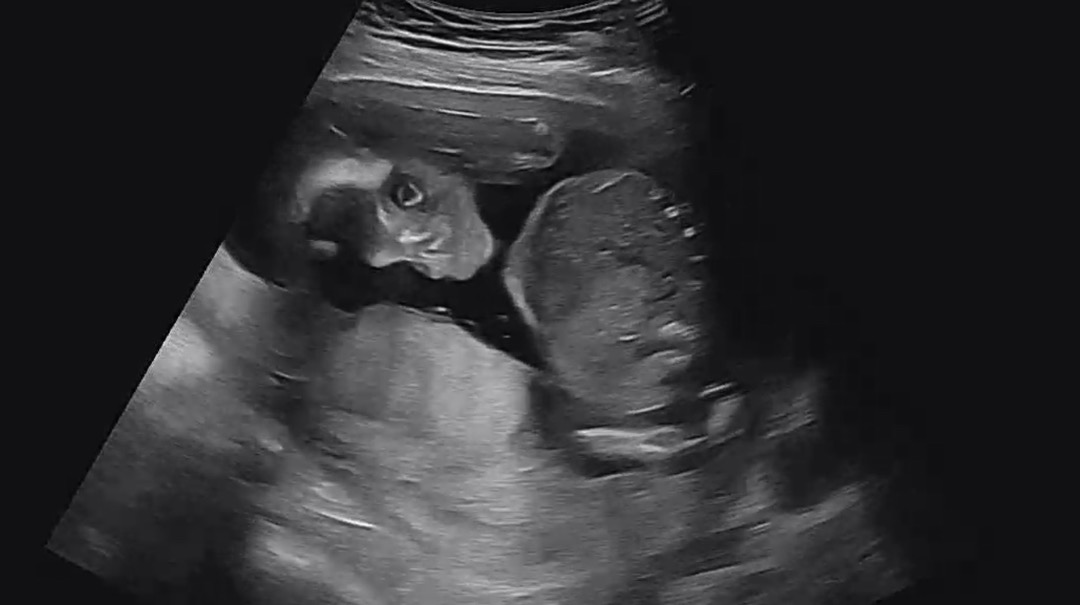

눈 뜨고 있는 태아

초음파 보고있는데 눈떳어요..ㅋㅋㅋ 처음봐서 신기해요ㅎㅎㅎ약간 무섭기도..ㅋㅋㅋ

눈뜬 게 아니라 초음파라서 안구를 본 거에용ㅋㅋ 저렇게 크게 떠지지 않잖아요~

아 그렇군요!! 어쩐지.. 눈이 너무 동그랗다했어요ㅋㅋㅋㅋㅋ푸하하🤣🤣